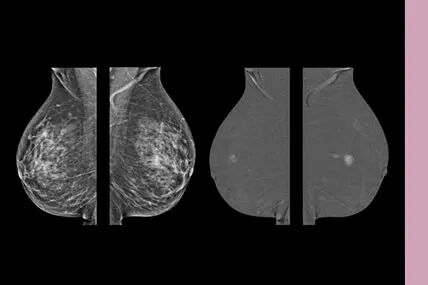

乳腺对比增强 (CESM)更精准诊断疾病

乳腺机技术的发展已经进入功能诊断时代,GE创新的CESM对比增强技术正在引领乳腺功能成像、病变定性诊断。CESM技术利用碘剂K缘效应,摄取不同能量下的乳腺影像,提升乳腺X线检查的敏感性和特异性,通过融合与重建,显示实质性肿块、微钙化,帮助医生进行更为精准的诊断,同时一次检查获取更多信息,节省患者时间和费用。尤其对于亚洲女性乳腺相对致密的特性,上万例临床诊断结果显示,乳腺对比增强技术提高了敏感性和特异性,对于高危人群乳腺筛查和临床诊断帮助很大,有助于明确病灶,指导治疗,以及术后评估。